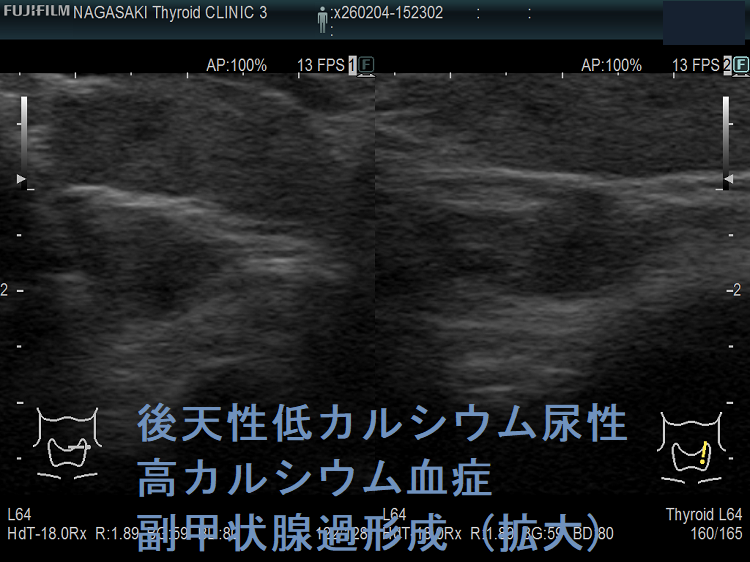

下は、隈病院の研究会資料から転載させていただきました。

後天性低カルシウム尿性高カルシウム血症は、副甲状腺・腎尿細管のカルシウム感受性受容体(Caセンサー:CaSR)に対する自己抗体が原因。高カルシウム血症が原因なのに、

- 副甲状腺のPTH分泌が抑制されない

- 腎のカルシウム排泄が促進されない